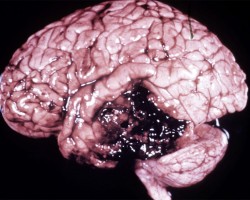

- Cerebral contusions, typically in areas where brain parenchyma rubs against skull bone (i.e. inferior temporal and frontal lobes)

- Coup contusions occur on the side of the trauma.

- Countercoup contusions occur on the opposite side of the site of impact.